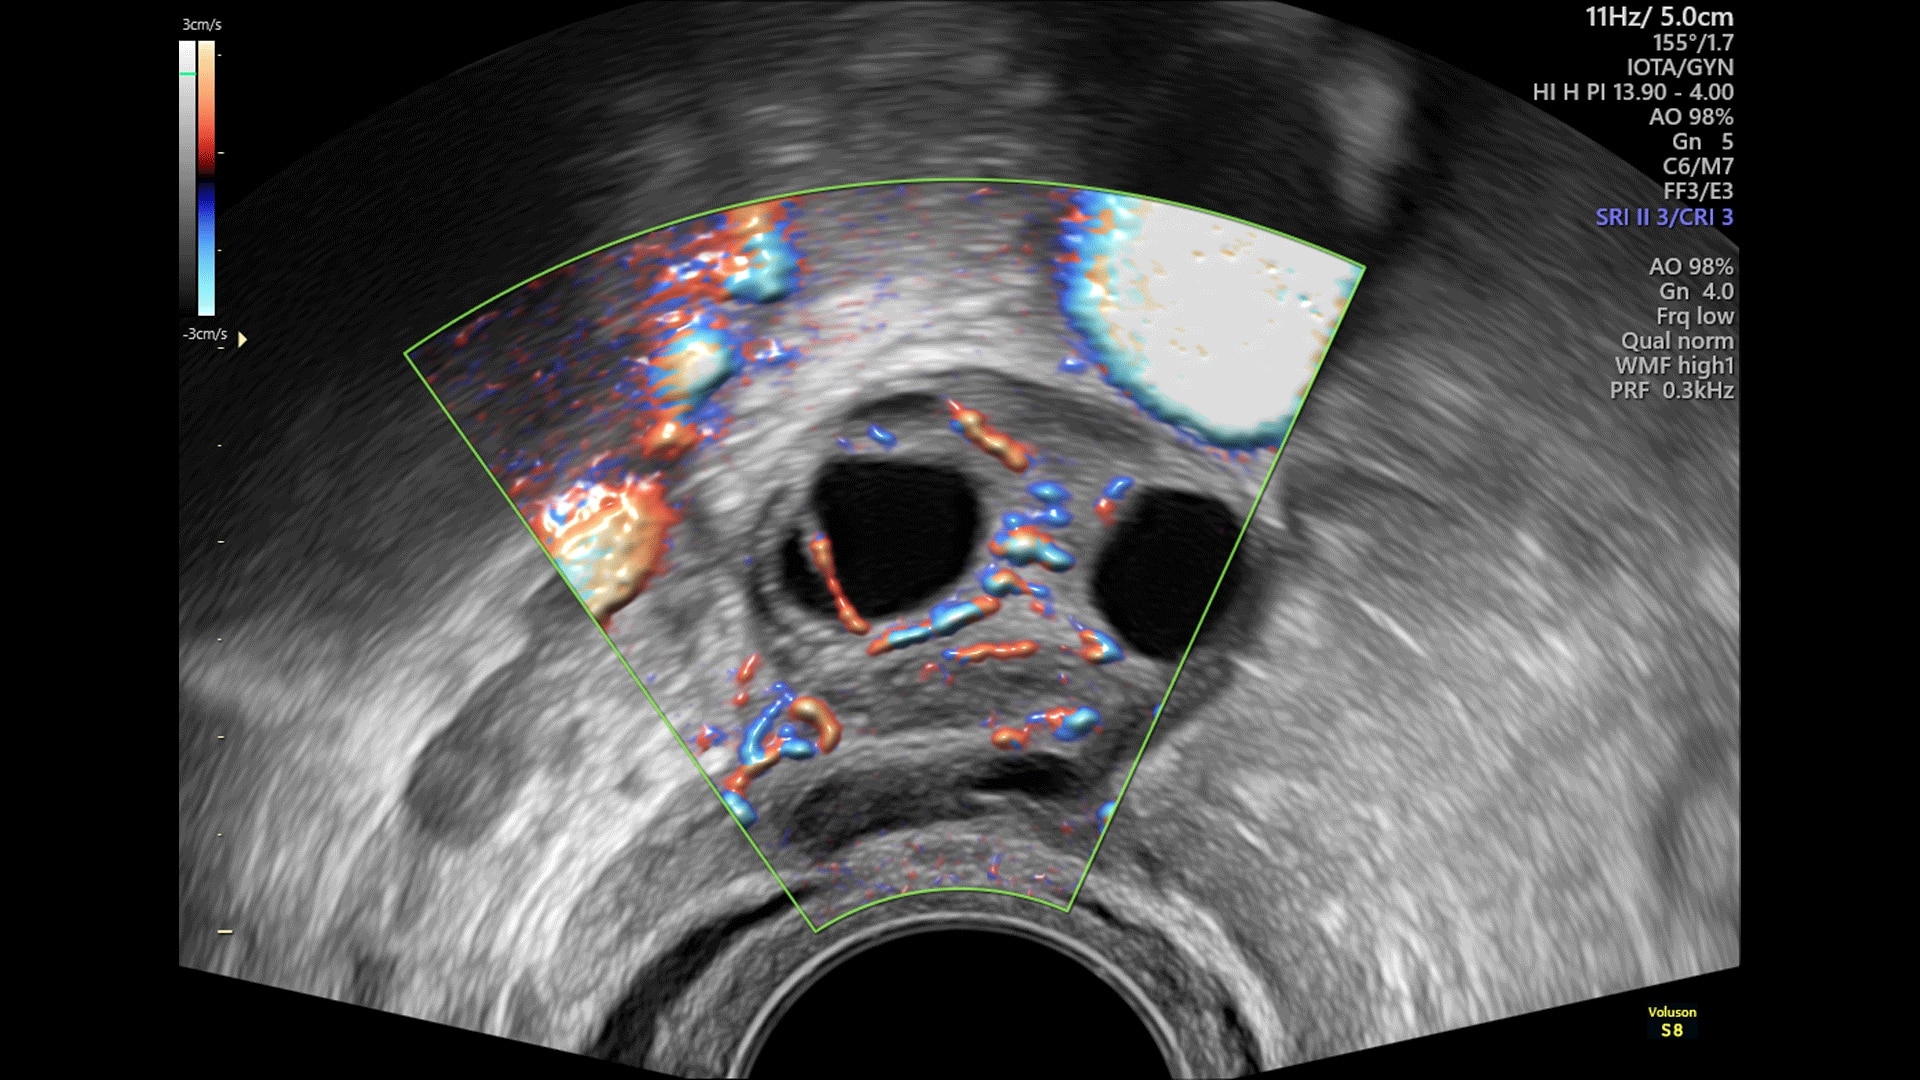

Exceptional Color Sensitivity

Enhance visualization of small vessels and borders of the fetal heart with Radiantflow™; powering greater color sensitivity for a more dynamic 3D-like appearance.

SonoAVC™follicle & SonoAVCantral

SonoAVC™follicle & SonoAVCantral automatically calculate the number, dimensions, and volume of hypoechoic structures for follicle monitoring or antral follicle count.